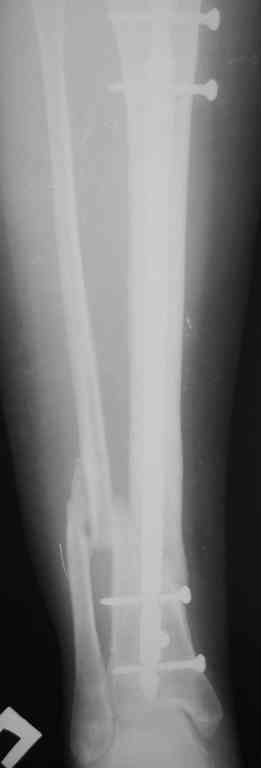

Re: Ложный сустав голени перелом штифта

Прилагаются.